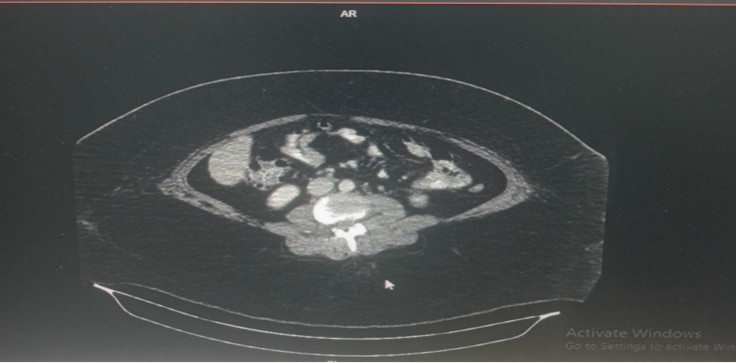

Due to her progressively worsening obesity and its impact on her daily life, she was admitted for an elective laparoscopic sleeve gastrectomy. The surgical procedure was performed successfully without any intraoperative complications, and a drain tube was placed to monitor postoperative output. Her immediate postoperative recovery was uneventful. She tolerated the prescribed diet progression, had stable vital signs, and her pain was well controlled. She was discharged on the 6th postoperative day in good condition with appropriate postoperative instructions. On the 13th day after discharge, the patient returned with complaints of severe abdominal pain. A CT scan of the abdomen and an abdominal ultrasound were performed to rule out postoperative complications such as gastric leak or intra-abdominal collection. Both imaging studies showed no evidence leak or abnormal findings.

K/C/O sleeve gastrectomy with post-operative status shows: No obvious evidence of contrast leak at present. No obvious evidence of free fluid / intra-abdominal fluid collection / abscess. Focal areas of altered density in the subcutaneous plane of the anterior abdominal wall on the left side.

Fig (3): Pelvis with Contrast